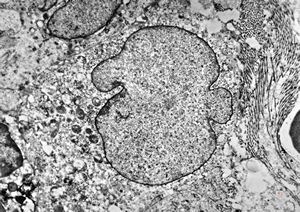

M,3m. | type II. pneumocyte